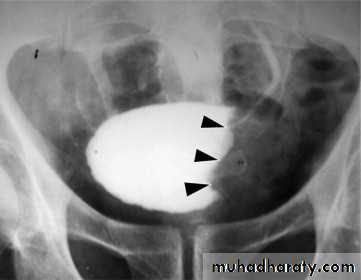

Schistosomiasis

Infestation by s.hematobium

Calcification is most important feature, mainly in bladder & lower ureters , but may involve whole ureters .

In early stage inflammation may cause cobble stone appearance.

Bladder capacity not affected.Ddgx of bladder calcification :

1. schistosomiasis .2.tumor , TB, …